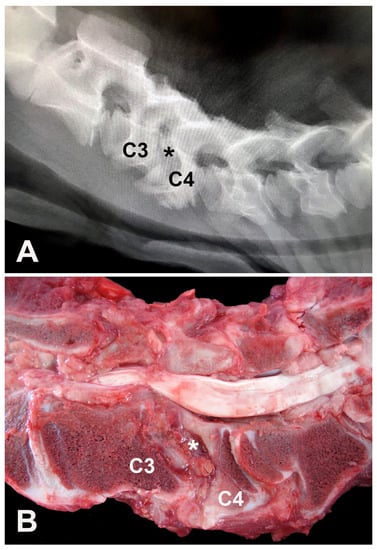

Haematological examination revealed leukocytosis (19.2 × 103 leukocytes/μL; reference range: 4–12 × 103 leukocytes/μL) by lymphocytosis (10.1 × 103 lymphocytes/μL; reference range: 2.5–7.5 × 103 lymphocytes/μL) and neutrophilia (7.6 × 103 neutrophils/μL; reference range: 0.6–4.0 × 103 neutrophils/μL). Biochemical abnormalities included hypoproteinemia (5.5 g/L; reference range: 6.74–7.46 g/L) by hypoalbuminemia (2.64 g/L; reference range: 3.0–3.55 g/L) and hypoglobulinemia (2.76 g/L; reference range: 3.0–3.48 g/L) [9]. Cerebrospinal fluid (CSF) analysis was unremarkable [7]. A CSF sample was referred for microbiological assay and tested negative. Lateral cervical digital radiographs identified the main finding of a cervical spondylopathy between the C3 and C4 vertebrae, causing stenosis of this vertebral canal due to misaligned vertebral bodies and abnormal endplates (C3 to C6) (Figure 1A). Dorsal dislocation of the C3 vertebral body was evident in association with near-total obliteration of its intervertebral foramen. The laminae of the C4, C5, and C6 vertebral arches appear to be small and abnormal, which alters the size and radiopacity of their intervertebral foramina. In the C2 to C6 articular processes, osteoarthrosis and bone proliferation are observed in the spinous processes. Ventrally to C4, bone proliferations were also noted. Spinal cord compression at the C3–C4 site was highly suspicious due to radiographic findings.

A presumptive diagnosis of CVSM causing spinal cord compression at C3 and C4 vertebrae was proposed, and, due to financial constraints, the owner elected euthanasia, and a necropsy was performed. Gross evaluation evidenced a ventral-dorsal misalignment between C3 and C4 vertebrae. The fourth cervical vertebra showed cranial articular surface malformation, abnormal metaphyseal growth plate development, and reduced vertebral body size and deformity. The medullary canal was also narrowed with focal compression of the cervical spinal cord (Figure 1B).

Figure 1. Four-month-old Nelore calf. (A) Latero-lateral digital radiograph of the cervical vertebral column showing intervertebral foramina with altered radiopacity, reduced intervertebral spaces, and misalignments between the endplates, more evident between the C3 and C4 vertebrae (asterisk) with material displacing the spinal cord ventri-dorsally and almost completely obliterating the corresponding intervertebral foramen, resulting in narrowing of the spinal canal and compression of the spinal cord. (B) Cervical vertebrae, longitudinal section, gross aspect. C3–C4 vertebrae misalignment (asterisk), reduced C4 vertebral body size and deformity, and focal compression of the cervical spinal cord.